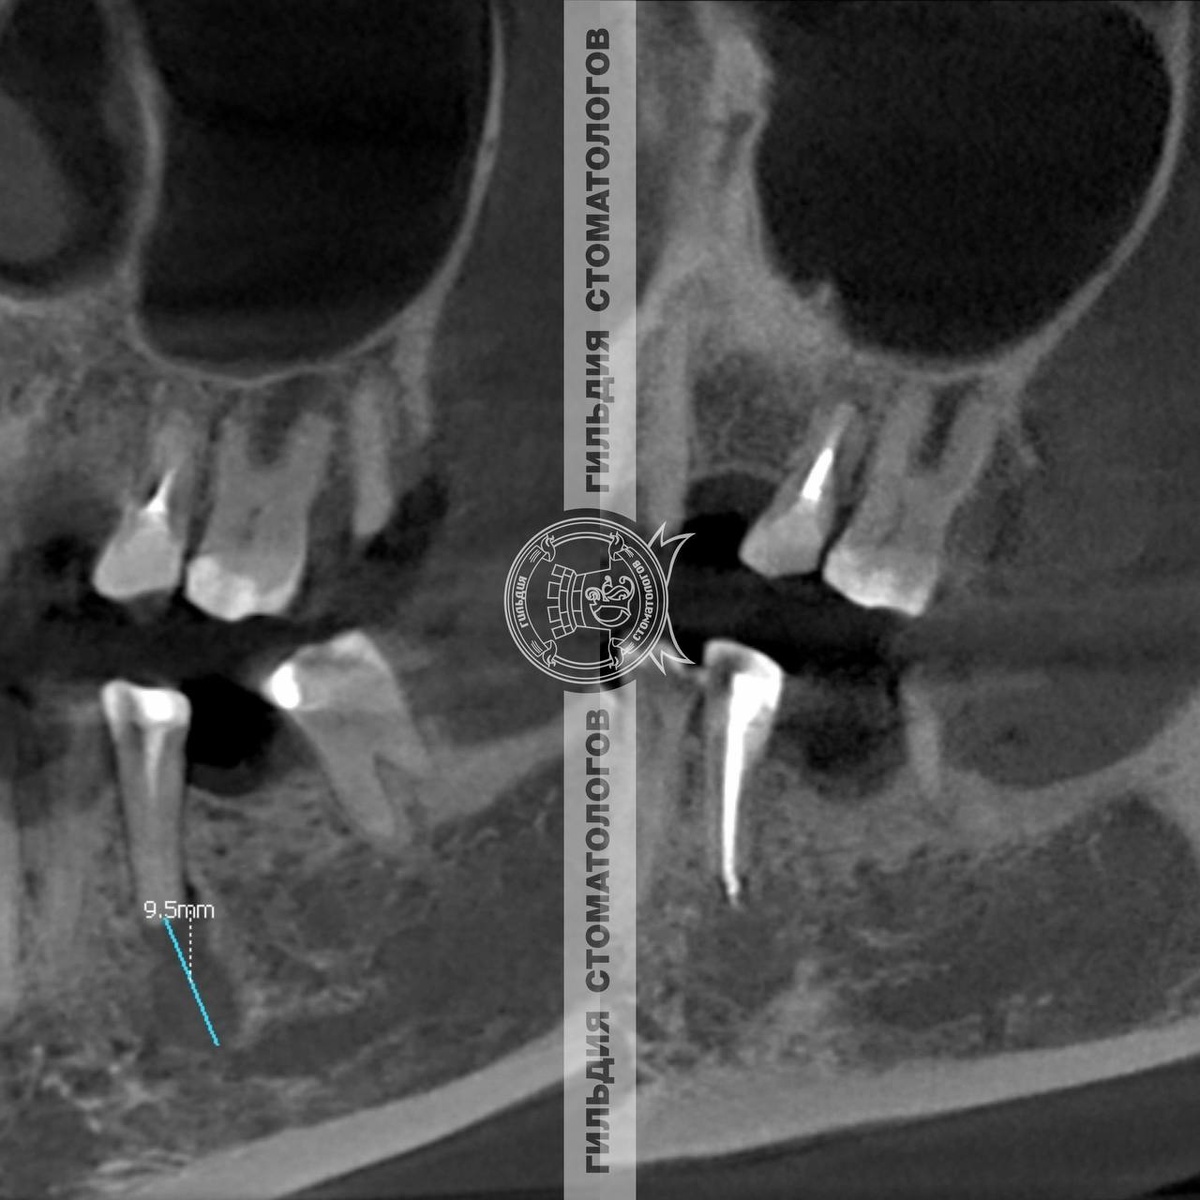

Однако, не всегда консервативное лечение бывает эффективным. Если размер кисты большой (более 10 мм), прогноз сохранения зуба ухудшается. Чем более запущенный процесс, чем больше объем потери костной ткани, тем хуже прогноз, связанный с сохранением зуба.